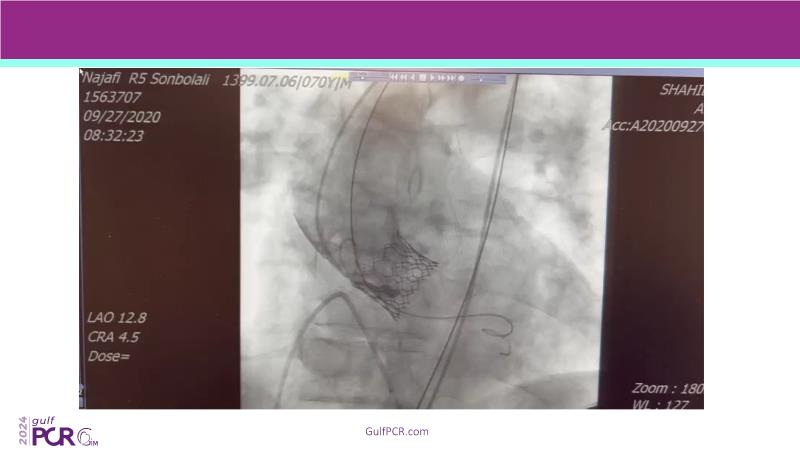

Stay ahead in TAVI innovation by exploring the advanced balloon-expandable Myval THV series. This session highlights the latest clinical data, optimal sizing and implantation techniques, and valuable real-world insights, including long-term follow-up results.

- To understand the best practices for Myval sizing and implantation technique for best outcomes